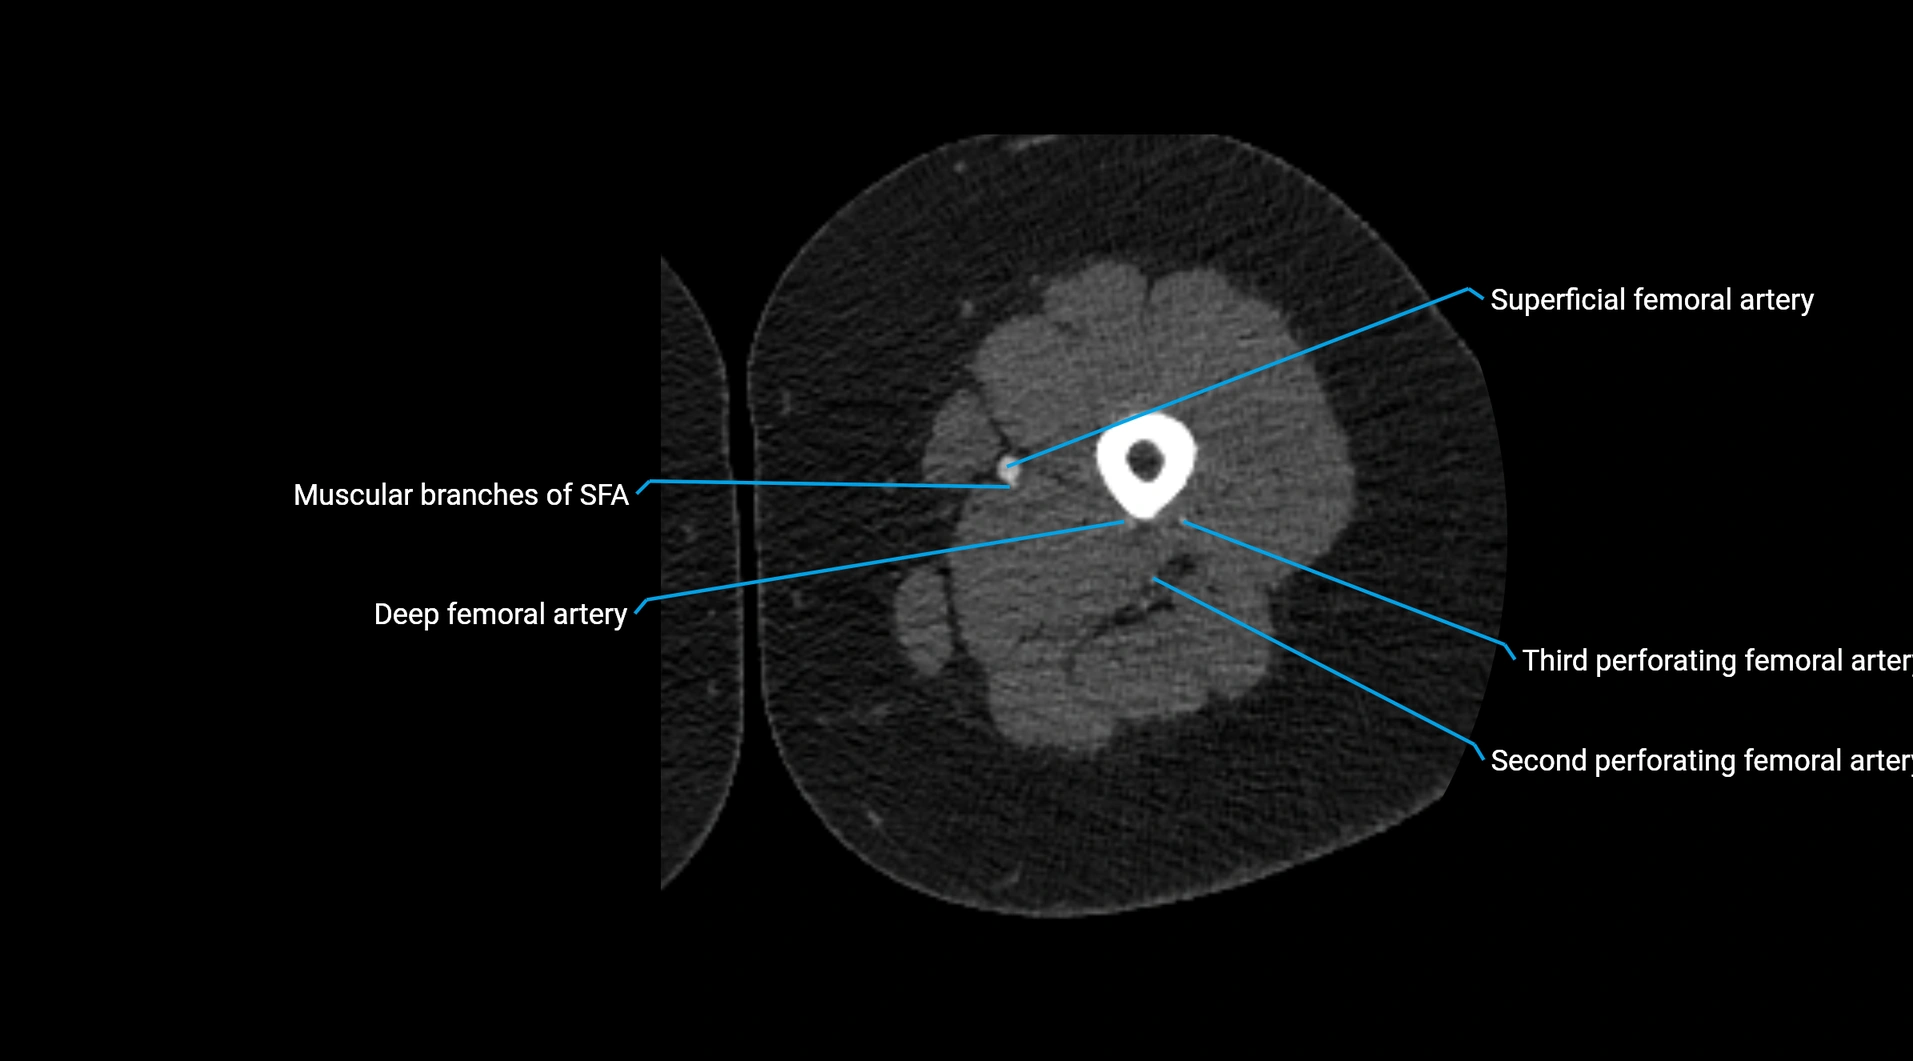

Contrast-enhanced CT (CTA):

• Gold standard for abdominal aortic imaging

• Provides excellent detail of lumen, wall, aneurysm, thrombus, and branch vessels

• Multiplanar and 3D reconstructions help in aneurysm measurement, stent graft planning, and dissection evaluation

• Detects acute rupture, traumatic injury, or occlusion with high sensitivity